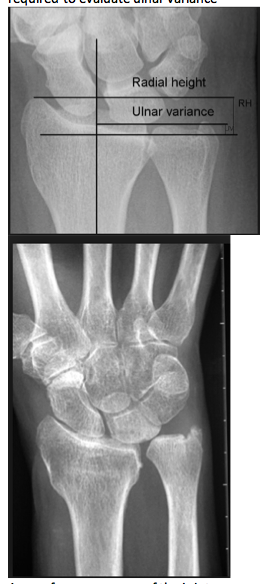

How is the load distribution in the wrist affected by ulnar variance?

How does position of the forearm affect ulnar variance?

A pronated grip view is the best to determine your ulnar varience

Pathophysiology of altered ulnar variance

Radiographic work-up for ulnar sided wrist pain

Ulnocarpal Abutment